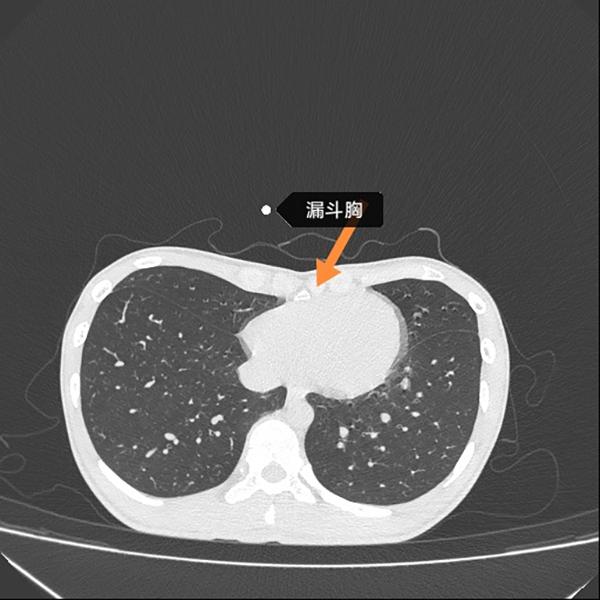

术前CT(图3)

胸外科主任崔健在接诊后,为患者安排查体及影像学检查(图1、图3)。通过检查,发现患者为漏斗胸,诊断明确。在充分分析患者病情的基础上,崔健认为患者符合Nuss手术适应症,在严格进行术前评估及准备,并征求患者及家属的意见后,崔健和胸外科医疗团队为患者实施了Nuss手术,即微创漏斗胸矫正术。术后胸廓矫正满意(图2),患者于术后1周顺利出院。

1、漏斗胸是胸骨连同肋骨向内向后凹陷,呈舟状或漏斗状,胸骨体剑突交界处凹陷最深[1]。新生儿发病率为0.1%~2.5%,以男性为主[2]。临床表现[3]:婴儿期漏斗胸压迫症状较轻者常未被注意。患儿常体形瘦弱,不好动,易患上呼吸道感染,活动能力受限制,活动后出现心慌、气短和呼吸困难。体征除胸廓畸形外,常有轻度驼背、腹部凸出等特殊体型。X线侧位胸片可见下段胸骨向后凹陷,与脊柱间距离缩短,CT图凹陷更为确切清晰。